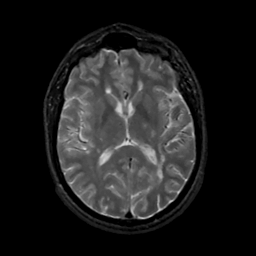

MR Study #14, June 2, 1991 -- Slice #27